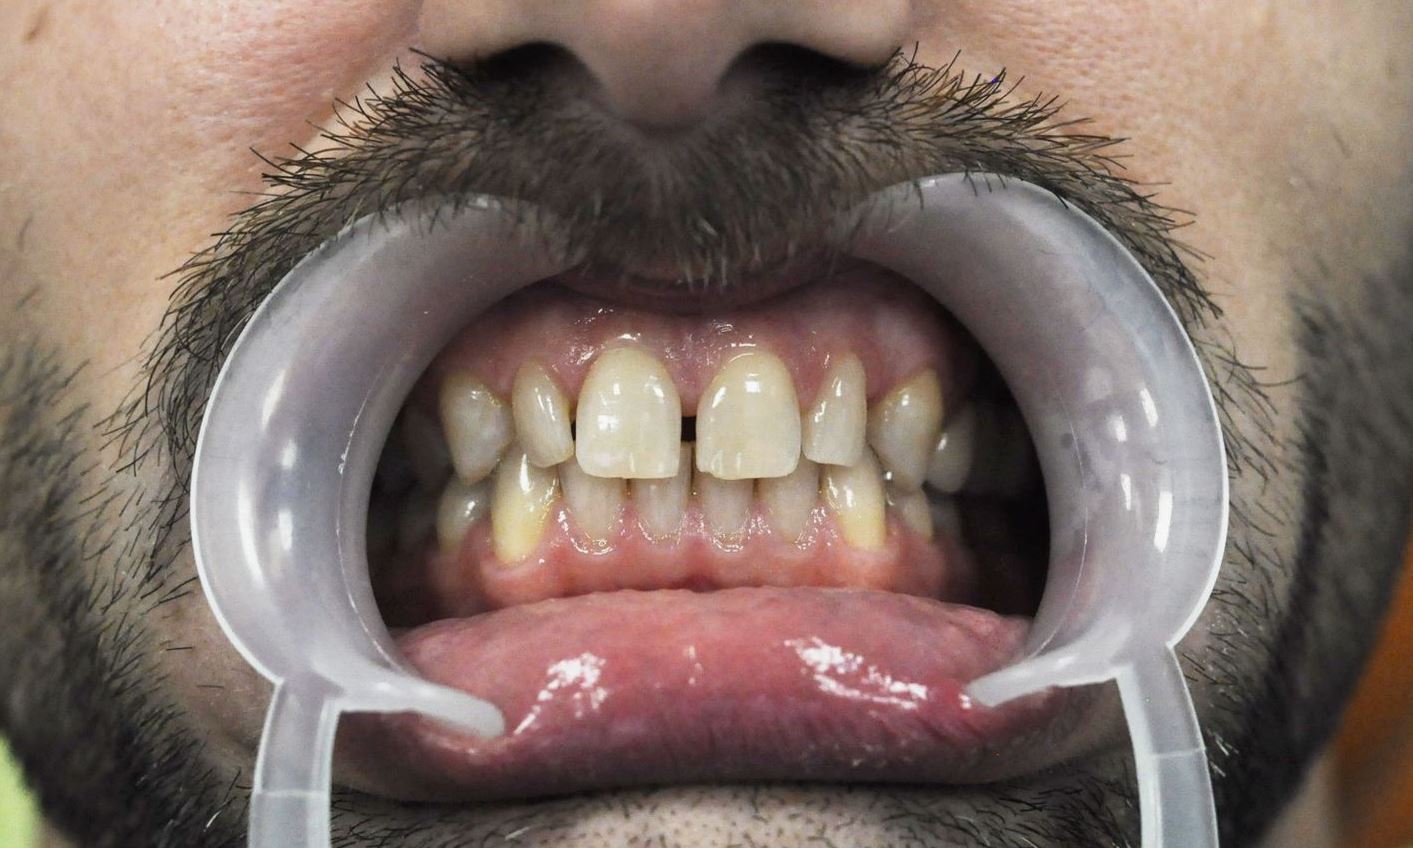

Pacjent przed zabiegiem

Pacjent po zabiegu flow injection - dolny łuk zębowy

Pacjent przed zabiegiem

Pacjent po zabiegu flow injection - górny łuk zębowy